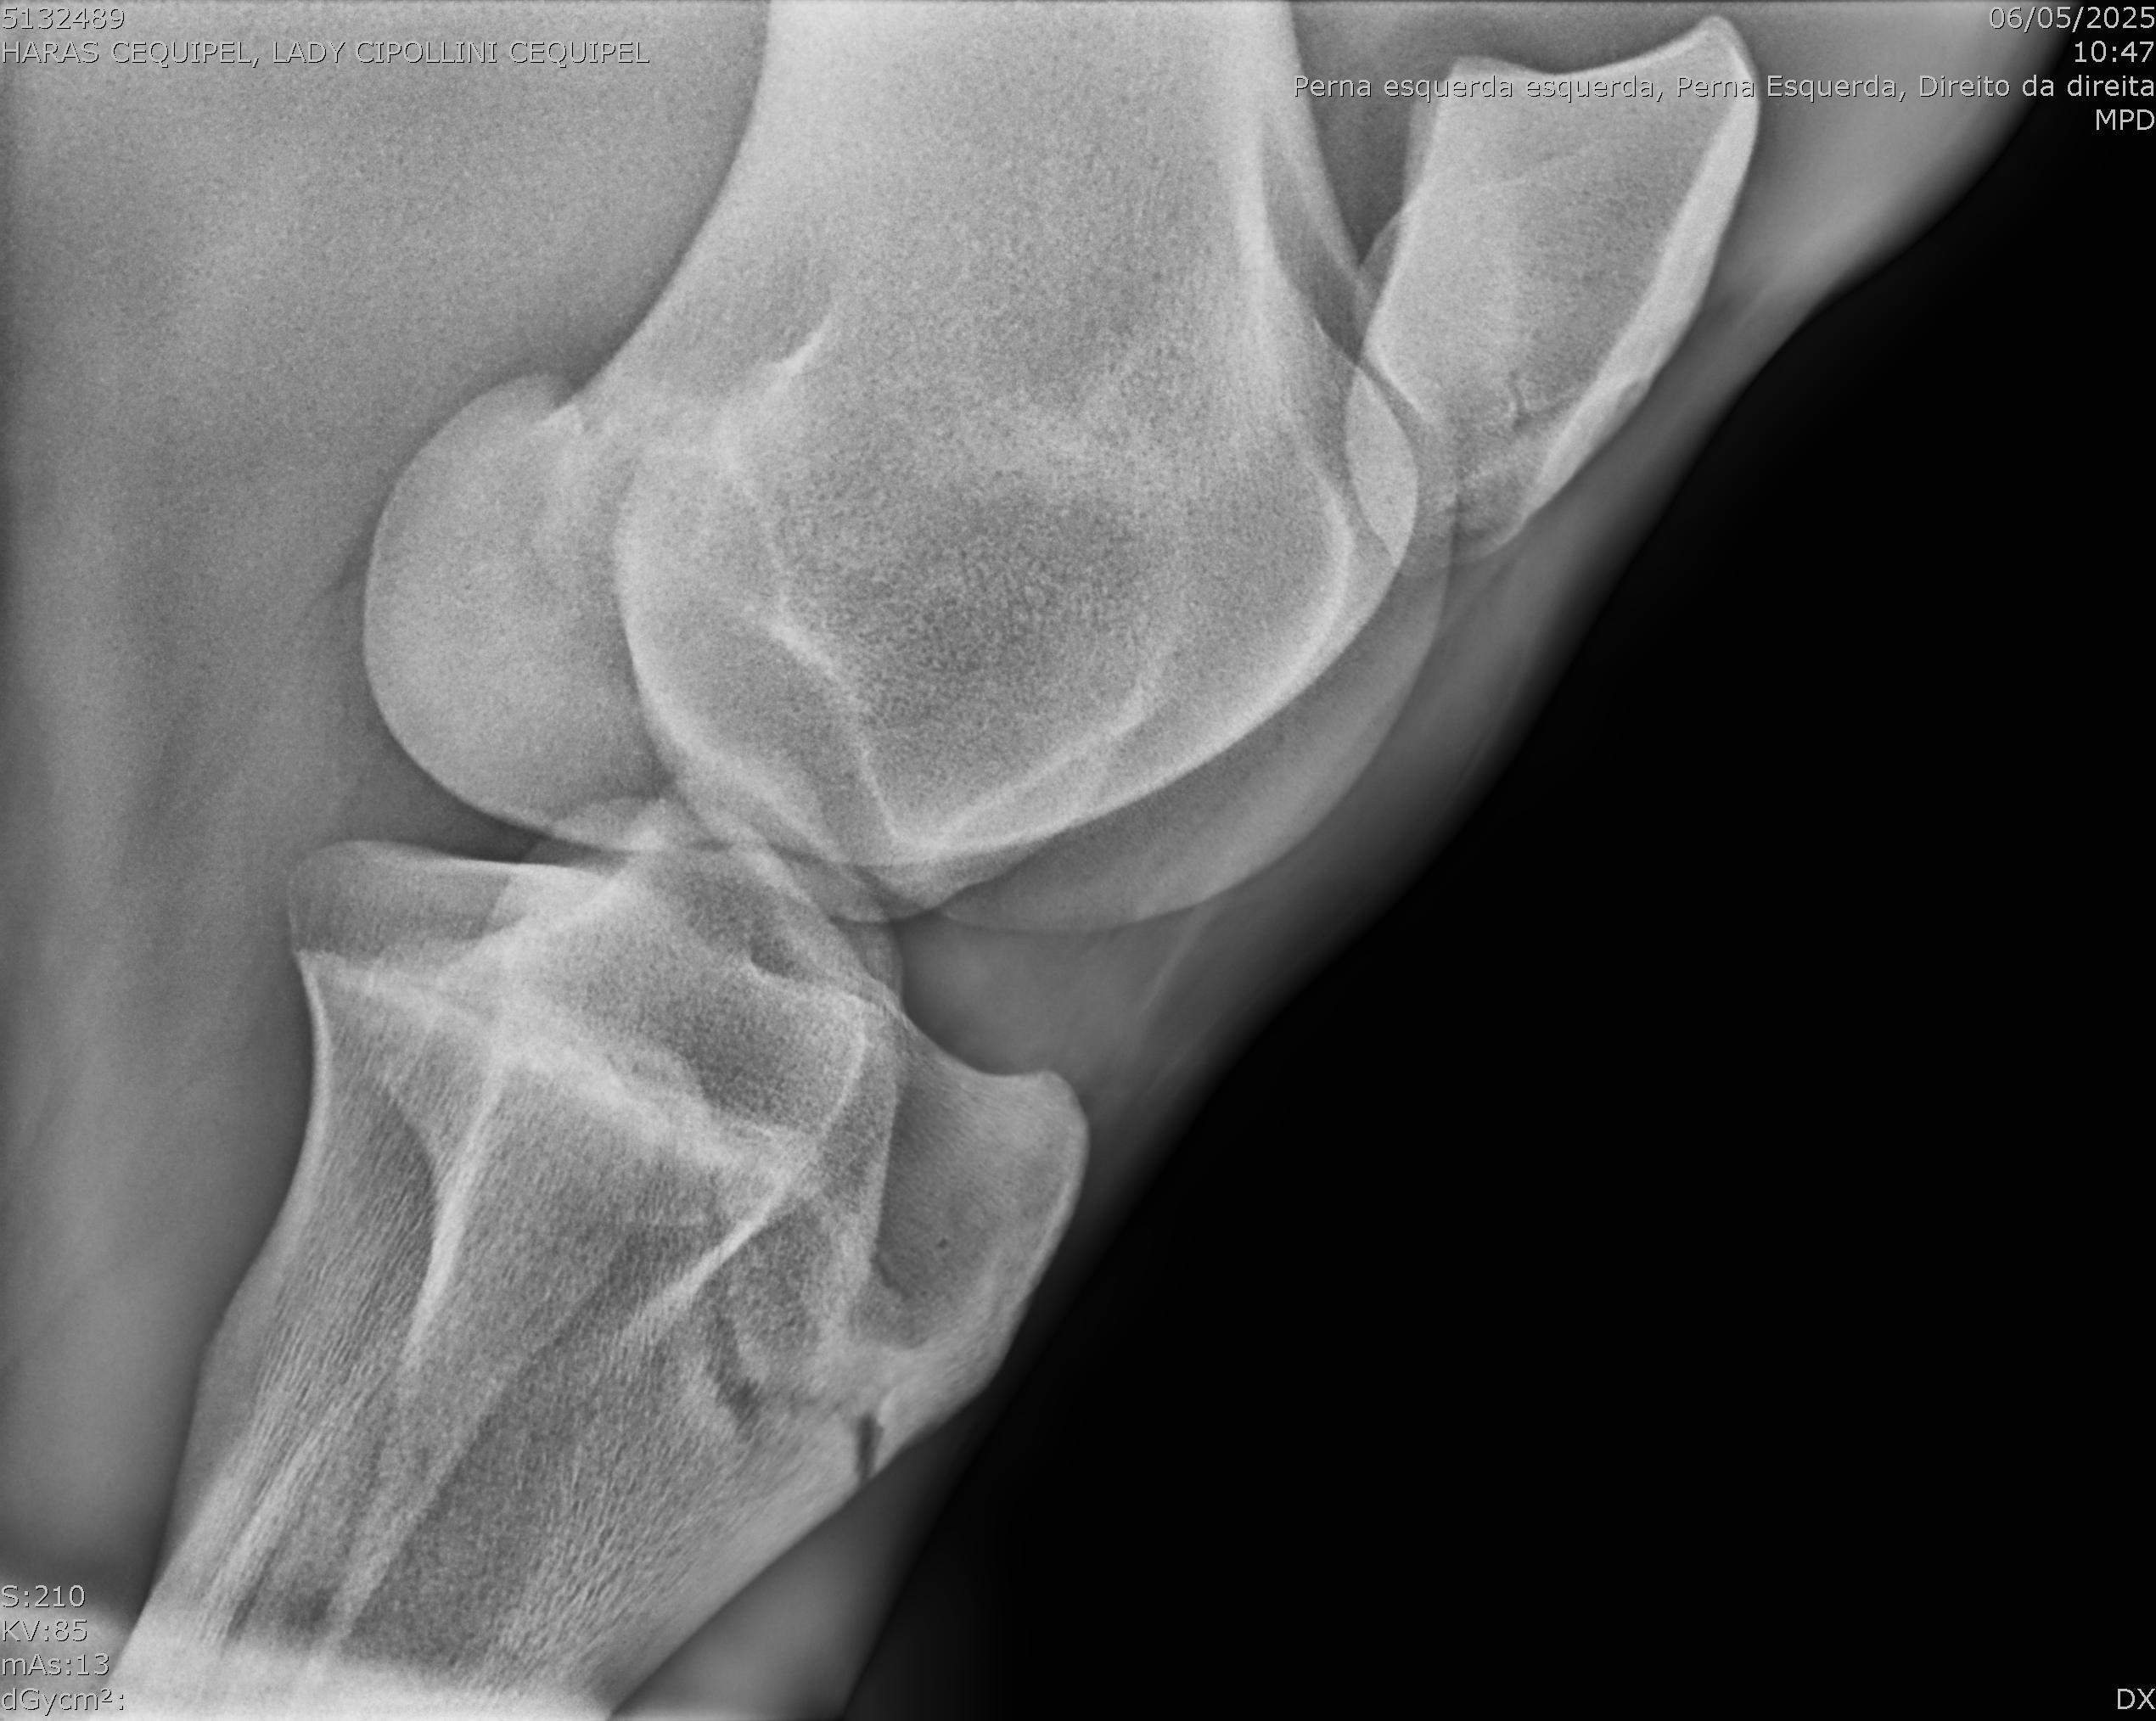

:: RAIOS-X DO LOTE